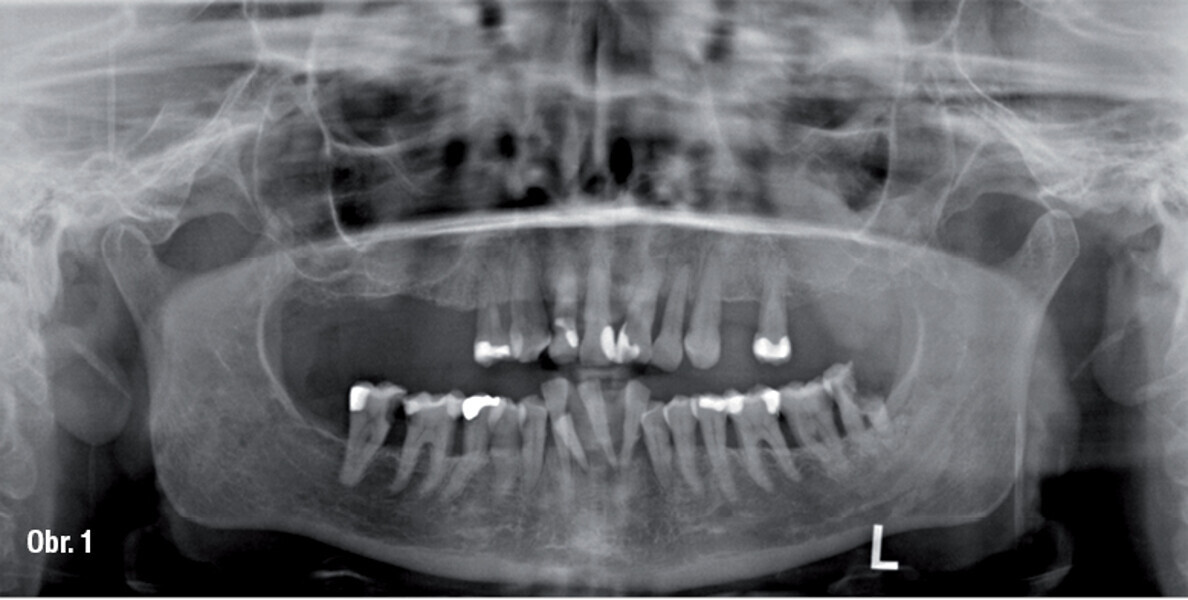

Zubní implantáty – od týmového plánování k esteticky úspěšnému výsledku